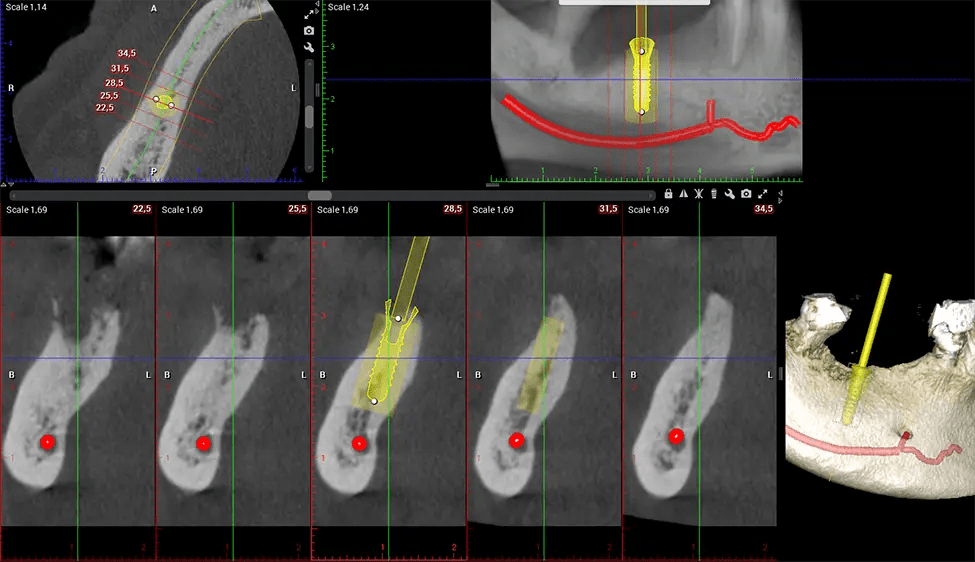

Cuando se combina con extracciones, colocación de implantes dentales o injertos óseos, la tecnología CBCT puede brindarle una experiencia más rápida y mucho más cómoda. Esto se debe a que la imagen 3D proporciona una imagen más detallada de toda su cavidad bucal, lo que le permite a su dentista guiarlo en cada paso del proceso antes de que ocurra. Esto a menudo ayuda a los pacientes a sentirse más preparados y cómodos en general, especialmente si han tenido una experiencia traumática con tratamientos dentales anteriores.

Primero se coloca al paciente en el escáner CBCT, que normalmente consta de un brazo giratorio que alberga la fuente de rayos X y un detector. La cabeza del paciente está inmovilizada para garantizar una captura de imágenes precisa. La fuente de rayos X y el detector giran alrededor de la cabeza del paciente, capturando varias imágenes de rayos X desde múltiples ángulos. A medida que la fuente de rayos X gira, emite un haz de rayos X en forma de cono hacia el detector. El detector captura las imágenes de rayos X, que luego son procesadas por el software CBCT.

Después del proceso de escaneo, las imágenes de rayos X capturadas son procesadas por el software CBCT, que aplica algoritmos para reconstruir una imagen 3D detallada del área escaneada. El software recopila estas imágenes de rayos X individuales y crea una representación digital en 3D de la anatomía del paciente. El dentista o el radiólogo pueden ver y analizar la imagen CBCT 3D reconstruida. Esta imagen se puede manipular, rotar y acercar o alejar para examinar estructuras específicas y evaluar la condición del paciente.

Planmeca Viso G7 CBCT (Cone Beam CT Scan) está diseñado para superar las demandas de los líderes de la industria, los especialistas y las grandes instituciones. Tiene un gran sensor de ø25×30 cm con cuatro cámaras integradas. Puede capturar tamaños de volumen ilimitados, desde ø3×3 cm hasta ø30x30cm, capturando el casquete escutelario a través de C7 en la columna cervical. Planmeca Viso G7 ofrece el escaneo de volumen único más grande de la industria de ø30×19 cm. Está preparado para manejar modalidades de imágenes avanzadas como la tecnología Planmeca ProFace® y Planmeca 4D™ Jaw Motion. El soporte occipital para la cabeza permite una visión sin obstáculos del tejido facial.

Nuestra tecnología SCARA patentada permite a los médicos capturar verdaderas alas de mordida extraorales que son tan precisas para detectar caries como una serie de alas de mordida 2D, pero con la mitad de la dosis de radiación. Con nuestras alas de mordida, los médicos pueden ver los ápices de los dientes en ambas mandíbulas, lo que proporciona una visión más completa de la anatomía de los pacientes.